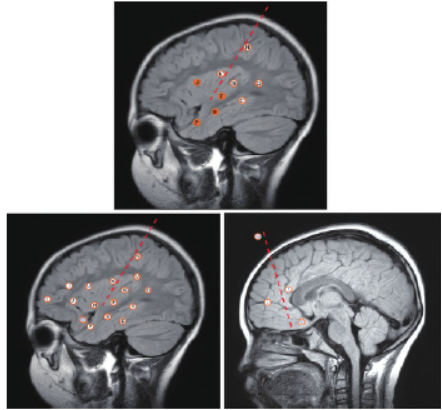

1.2 颅内电极植入设计及毁损

患者为非下丘脑错构瘤发笑发作,根据解剖-电-临床分析,考虑颞叶为第一核心致痫灶,额叶及前扣带回为第二核心致痫灶,围绕两个核心假说设计电极植入方案,排除手术禁忌后在机器人引导下植入颅内电极,植入后行颅内视频脑电监测捕捉发作,明确致痫灶起源后行经皮层电极电刺激脑功能区(mapping)检查,分析致痫灶与功能区的关系。根据颅内脑电图结果及mapping 结果,予以致痫区毁损,先予以时长40 s、功率2 W 预毁损,观察患者毁损后无功能障碍,再予以时长90 s、功率3.5 W 正式毁损,毁损完毕后拔出颅内电极,复查头部CT 无出血。见图2。

图2 颅内电极植入示意图及电极植入路径。P:颞极外侧面-颞极内侧面; B:颞中回-海马头; C:颞中回-海马体; D:颞中回后部-扣带回峡部; F:颞上沟-岛叶后部腹侧; G:颞横回-第2 岛长回下部; J:额下回三角区-第1 岛短回; K:中央下回-第3 岛短回; N:顶上小叶-第1 岛长回; L:额下回-前额叶内侧面; I:额下回-前扣带回; Q:额中回-ACC-眶额回内侧面; O:额下回一眶额回额底一BA25 区下部